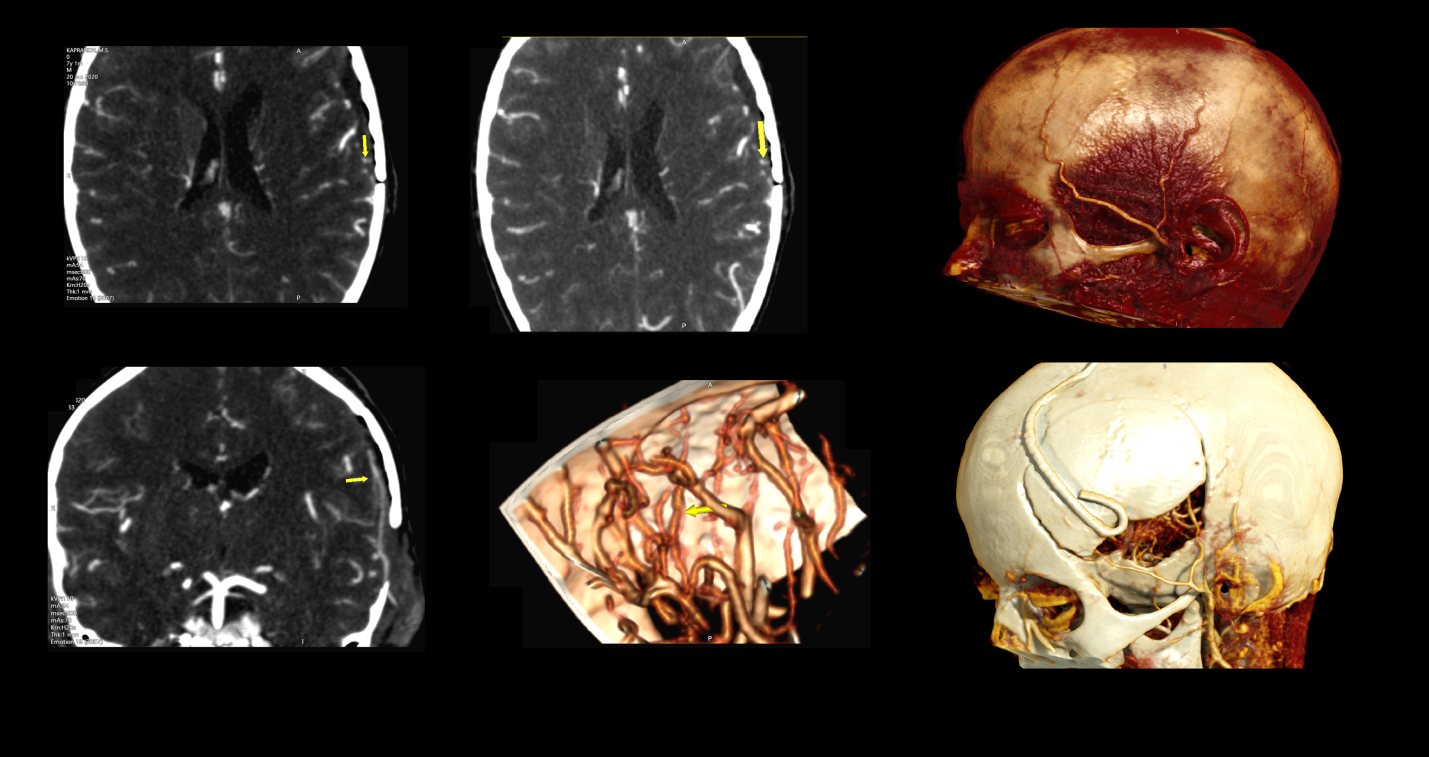

На предоперационных перфузионных картах до выполнения ЭИКМА отчетливо демонстрируется дефицит церебральной гемодинамики в корковых и субкортикальных зонах левой лобной и теменной областях, характеризующийся снижением показателей скорости мозгового кровотока (rCBF) в среднем до 35 мл\100г\мин (при средней норме 44-56 мл\100г\мин)  и удлинением времени транзита крови (MTT) в средних значениях до 6.7 сек при сопоставлении с контралатеральным полушарием превышающие значения в 1.5 раза (4.4 сек, при относительной норме средний транзит крови составляет менее 6 сек). Таким образом, показатель MTT наиболее чувствительный маркер изменения кровотока (удлинение данного показателя свидетельствует об наличии перфузионного дефицита) являясь предиктором гиперперфузии.

Спустя 5 дней после наложения ЭИКМА на перфузионных картах отмечается заметное улучшение показателей СBF и МTT на стороне анастомоза: повышение показателей CBF в среднем до 39 мл\100г\мин, и укорочение MTT до 5.4 сек (что, в свою очередь, укладывается в относительную норму).

Исходя из данных КТ перфузии, стоит сделать вывод, что после выполнения ЭИКМА по поводу односторонней субокклюзии левой СМА даже в раннем постоперационном периоде, данная операция приводит к восстановлению дефицита церебральной гемодинамики, тем самым снижая эффект «обкрадывания».